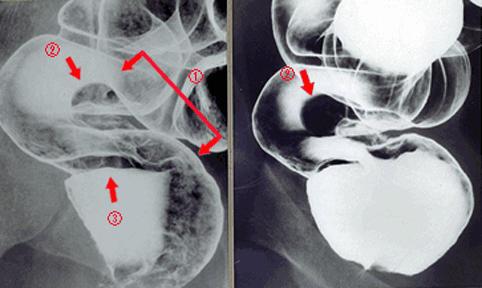

Posted by: Tokyo Pref., Centro Nacional de curaciones de Cáncer, Hospital Central y Centro Kyusyu de Curaciones de Cáncerc

Caso TIC(Conferencia TeleImágen de varios puntos del Tubo Digestivo en conjunto)

1999/01/01 |

femenino |